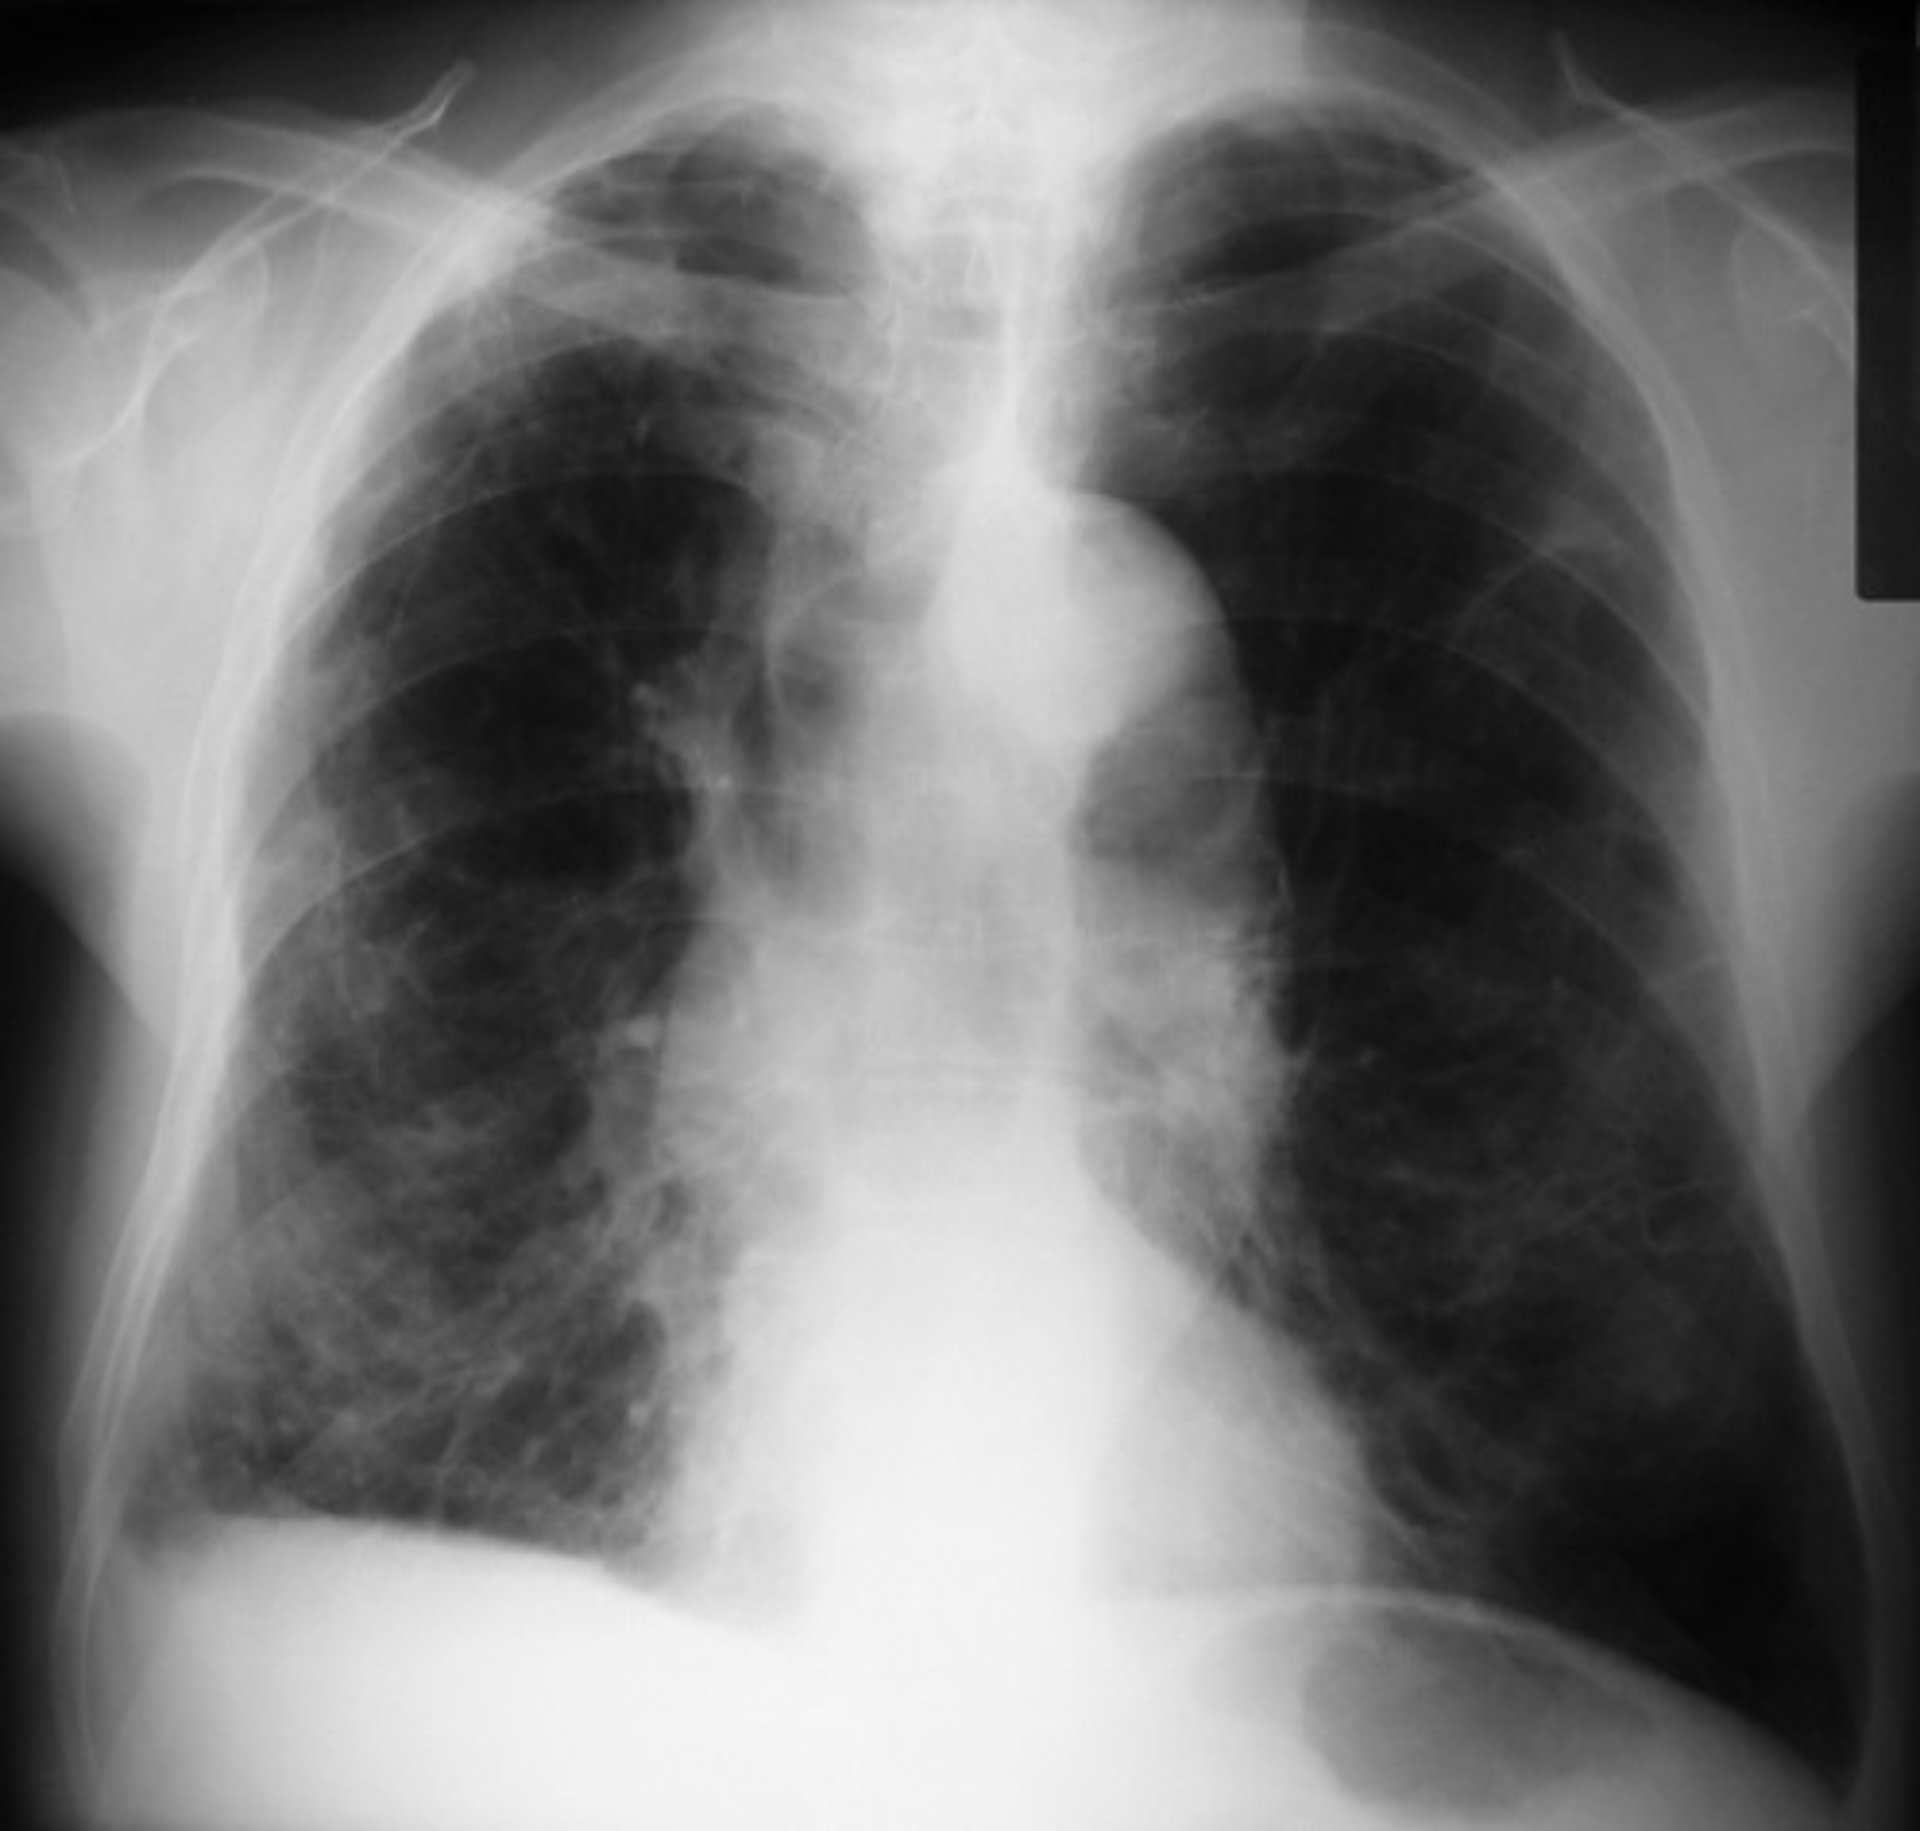

El desarrollo pulmonar puede explicar por qué algunos no fumadores contraen EPOC

El desarrollo pulmonar puede explicar por qué algunos no fumadores contraen EPOC - FLICKR//PICASA - Archivo

"Este trabajo, derivado del análisis cuidadoso de imágenes pulmonares de pacientes con EPOC, muestra que un desarrollo pulmonar anormal puede representar una gran proporción del riesgo de EPOC entre los adultos mayores --señala James Kiley, director de la División de NHLBI de Enfermedades pulmonares--. Se necesita más investigación para comprender qué impulsa este hecho y para idear posibles intervenciones".

Para averiguar si las vías respiratorias pequeñas podrían ser las culpables de la EPOC en personas que no fumaban o que tenían otros factores de riesgo, un equipo dirigido por Smith examinó los registros de más de 6.500 adultos mayores que participaron en tres estudios que incluyeron a fumadores y no fumadores con y sin EPOC.

Cada estudio, el Estudio Multiétnico de Aterosclerosis (MESA), el Estudio de los Pulmones, el Estudio de Subpoblaciones y Medidas de Resultados Intermedios en la EPOC (SPIROMICS) y el estudio de la Cohorte Canadiense de Enfermedad Pulmonar Obstructiva (CanCOLD), evaluaron la disanapsis usando tomografías computarizadas (CT) de los pulmones.